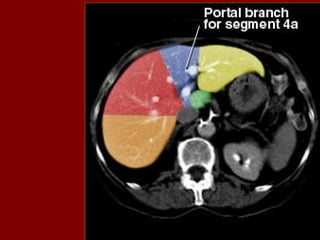

INCISÃO SOBRE A VEIA HEPÁTICA MÉDIA.

INCISÃO SOBRE A VEIA HEPÁTICA ESQUERDA.

INCISÃO SOBRE AVEIA HEPÁTICA MÉDIA.

INCISÃO SOBRE AVEIA HEPÁTICA ESQUERDA.